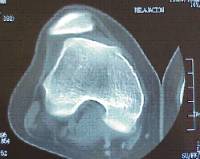

Es una patología ocasionada por una isquemia transitoria del hueso subcondral pudiendo progresar hasta llegar a provocar el desprendimiento del mismo.

Se localiza con mayor frecuencia en el cóndilo femoral interno y su pronóstico varía en función de la edad de presentación (poco frecuente por debajo de los 10 años) y la estabilidad de la lesión.

El tratamiento pasa por limitar actividad deportiva de impacto , variar el eje de carga mecánico de la extremidad y puede ser necesaria la intervención quirúrgica.

Existen diferentes opciones de tratamiento quirúrgico en función de la estabilidad y localización del fragmento osteocondral (microperforaciones bajo control artroscópico , fijación in situ del fragmento osteocondral , empleo de injertos osteocondrales / mosaicoplastia ).